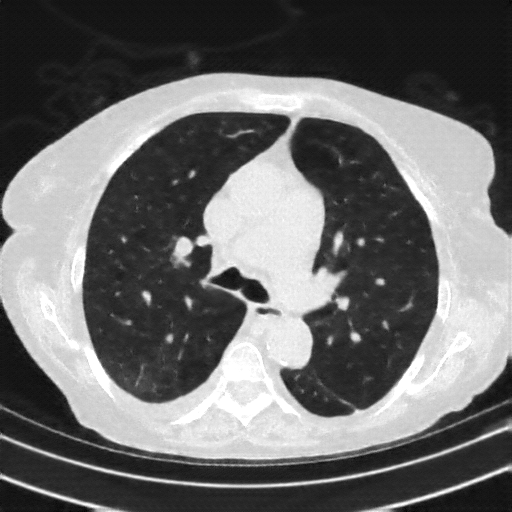

Targeted Slice 70 - Lung Window Analysis (Generated vs Real Venous)

0.598

Lung SSIM

162.3

Lung RMSE

72.3

Lung MAE

Average Lung Window Metrics Across All Slices (153 slices) - Generated vs Real Venous

0.579

Lung SSIM (Avg)

146.5

Lung RMSE (Avg)

66.3

Lung MAE (Avg)

Lung window (WL -600, WW 1500 β†’ Low βˆ’1350, High +150)

Original VENOUS CT scan

Actual HU range: [-1024.0, 150.0]